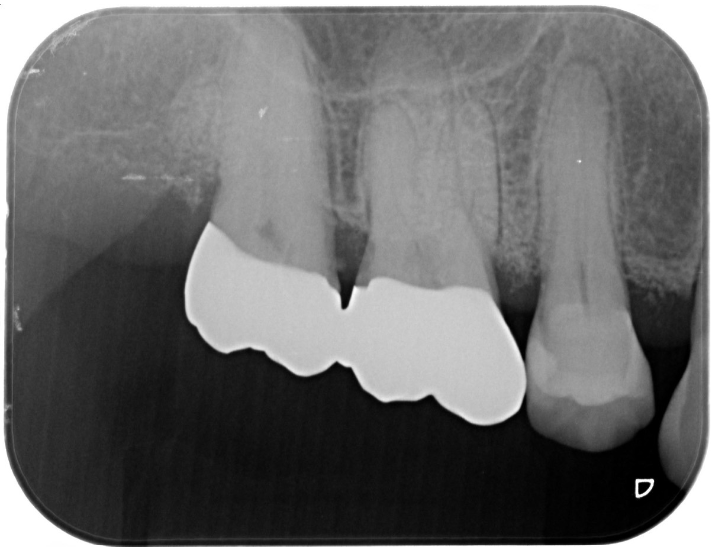

症例3

| 項目 | 詳細 |

|---|---|

| 患者様データ | 40代 女性 |

| 来院時の主訴 | 「歯がグラグラする。」 |

| 医院の診断 | 重度の歯周病、夜間歯ぎしり習慣 |

| 通院期間 |

1年 |

| 来院回数 | 8回 |

| 治療費 | 総額:220,000円(税抜) 【内訳】 歯周組織再生療法220,000円(費用は範囲によって異なります。) |

| リスクと副作用 | メインテナンスが必要、正しい歯磨き習慣が必要不可欠 |

| ここがこだわりのポイント!☝ | 痛みや手術時間が最小限となるよう、マイクロスコープを使用して小さい傷口の術式でオペを行なっています。 |